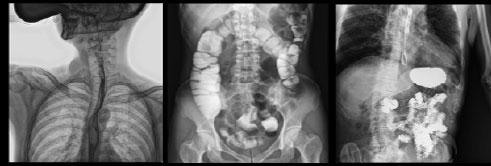

- Применяется в различных клинических рентгенологических исследованиях, таких как рентгенография, цифровая флюороскопия, контрастная и визуализированная точная съемка DR

- Функция Томосинтеза – передовая, самая современная технология визуализации, сочетающая технологию реконструкции конусно-лучевой компьютерной томографии и технологию цифровой обработки изображений (данная функция опциональна и предоставляется по предварительному запросу)

Рентгенологические исследования: рентгенография больших переломов костей и масштабное физическое рентгенографическое обследование, флюороскопия всех частей тела (грудная клетка, живот и т.д.), пищеводная ангиография, ангиография верхних отделов желудочно-кишечного тракта, полная ангиография желудочно-кишечного тракта, холангиография, Т-образная холангиография, ЭРХПГ, внутривенная пиелография, гистеросальпингография и т.д.